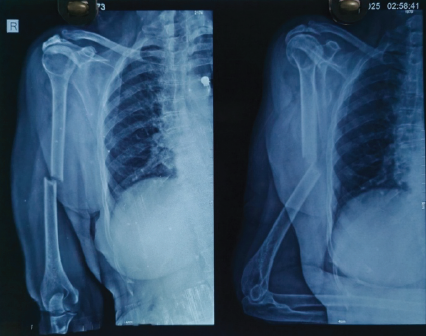

An 80-year-old right-hand dominant woman came to our clinic after a fall at home. She slipped while walking and landed squarely on her left arm. Pain was immediate and severe, and she was unable to raise the limb afterward. There was no loss of consciousness, seizure, or syncopal episode to suggest a systemic cause for the fall. Her medical history included well-controlled hypertension and early osteoarthritis of the knees. She had never sustained a fragility fracture and was not on corticosteroid therapy. On examination, she was comfortable, alert, and hemodynamically stable. The left arm showed diffuse swelling with a hint of angulation at the mid-arm level. The skin was intact, with no abrasions or breach. Palpation elicited marked tenderness over the midshaft of the humerus, with crepitus and abnormal mobility on gentle stress. Importantly, neurovascular assessment was intact – radial, median, and ulnar nerve functions were preserved, and both brachial and radial pulses were palpable. No features suggested a compartment compromise. Radiographs of the left humerus, in anteroposterior and lateral views, confirmed a sharply transverse mid-diaphyseal fracture (Fig. 1).

Figure 1: Pre-operative X-ray showing an atypical transverse fracture of midshaft

of humerus.

The fracture was clean, without comminution or extension into the joint. Cortical thinning consistent with osteopenia was noted, but there were no lytic lesions or features to suggest a pathological origin. The shoulder and elbow were normal on imaging. Given her age, the rare transverse configuration, and the limited biological potential of osteoporotic bone, surgical fixation was planned. After anesthetic evaluation and informed consent, we proceeded with antegrade locked intramedullary nailing under general anesthesia.